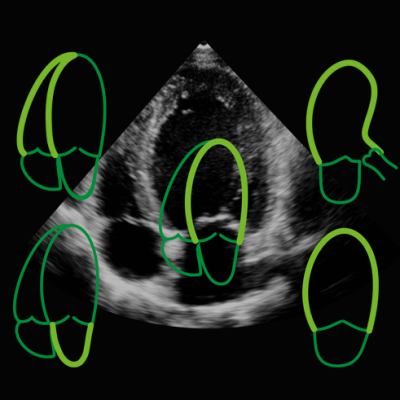

The software has measurement automation that uses artificial intelligence (AI) to improve the quality of information from diagnostic images. Automation is the key to reproducibility in the echo lab and the vendor has developed intelligent algorithms and AI-based data analytics that takes the user-variability out of the equation.

With the addition of AI-based data analytics and automation, structures within the heart such as the mitral valve and endocardium can be detected, modeled and dynamically tracked in seconds, all with minimal interaction from the user.